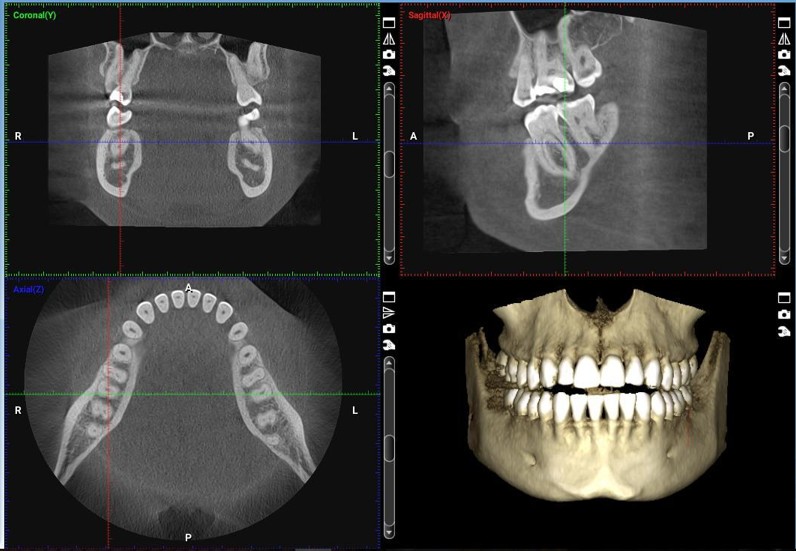

Cone Beam Computed Tomography (CBCT) is advanced 3D imaging technology that captures detailed, three-dimensional views of your teeth, jawbone, and surrounding structures. Unlike traditional dental X-rays that show flat, two-dimensional images, a CBCT provides a complete 360-degree view of your oral anatomy.

One of the most powerful aspects of CBCT imaging is that you can see what we see. We can show you three-dimensional images of your own mouth, helping you understand your condition and the proposed treatment plan. There’s something incredibly reassuring about being able to visualize exactly what’s happening and what we’re planning to do about it.